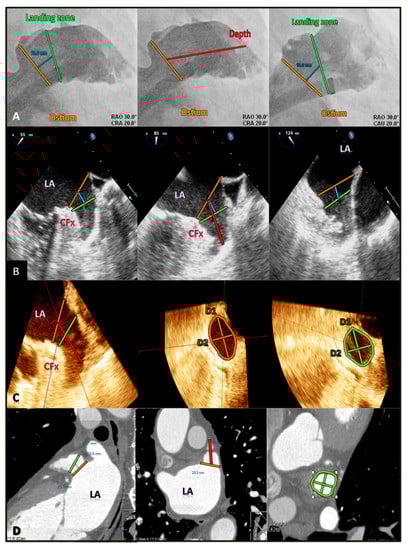

Angiography (Siemens Artis Zee, Forchhein, Germany) was performed during LAA closure by expert operators. After transeptal puncture, a 5-F marker pigtail was advanced into the LAA, and cineangiograms were performed in multiple projections to ascertain the LAA anatomy and measurements. Caudal projections were used to visualize the mid-distal LAA, whereas right anterior oblique cranial projections were used to visualize the ostium and proximal LAA. The LAA neck and lobes were identified by the use of contrast injections through the sheath from different angulations. The measurements of the ostium, landing zone (at 10 mm), and depth were taken at end-systole. The maximum diameters were recorded (Figure 1A). Measurements were made with angiography-dedicated software.

Standard measurements of LAA by different imaging modalities. (A) Selective angiography measurements at the echocardiographic ostium (orange line), landing zone (green line) at 10 mm (blue line) from ostium, and LAA depth (red line). (B) 2D TOE measurements of the ostium, landing zone, and depth. (C) 3D TOE standard measurements of ostium diameters and area, of landing zone diameters and area, and of LAA depth. (D) CCT multiplanar reconstruction images with measurements of the landing zone area, maximum and minimum diameter, and LAA depth. LA = left atrium; CFx = circumflex artery; D1 = maximum diameter; D2 = minimum diameter.

The OS measurements were calculated from the origin of the left circumflex artery to the tip of the left superior pulmonary vein, whereas the LZ measurements were calculated 10 mm deeper with respect to the LAA orifice. Finally, the LAA depth was generally measured from the orifice line to the apex of the LAA (Figure 1B). The 2D images were analyzed on-line.

Similar to TOE, OS and LZ diameters and areas, as well as LAA depth, were measured with reconstruction planes (Figure 1D).